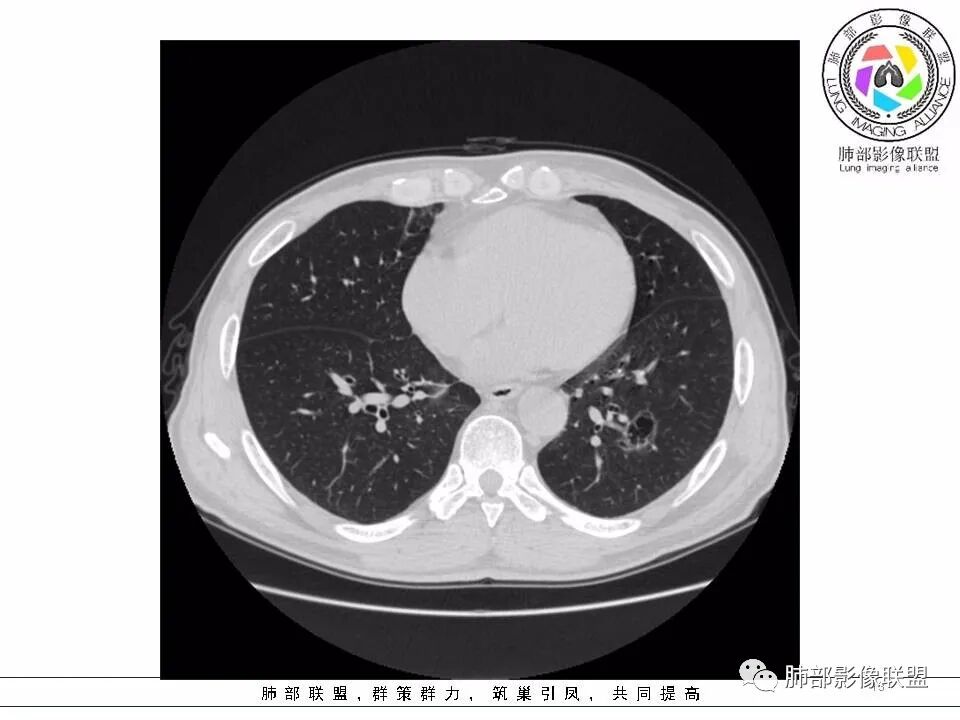

男,53岁。

间断发热半月余。半月前无明显诱因出现发热,体温波动于38℃,畏寒,轻咳,少量白痰,时有活动后胸闷气喘。无胸痛、心慌、乏力、盗汗、消瘦、咯血。于当地诊所予以头孢静脉输注一周,体温正常3天后再次出现体温升高。波动于37.2℃。实验室检查没有太多的问题。左肺下叶囊腔病变,壁比较薄,部分环壁局限性的增厚,边界毛糙,略显模糊,并见与支气管相连,未见明显的壁结节,而囊壁内见丝丝缕缕的索状影。考虑良性病变,毛霉菌感染或隐形性感染,鉴别寄生虫肺部感染。

老年男性,左肺下叶外基底段囊腔,壁厚薄不均,周围可见磨玻璃影,腔内密度不均匀,可见索条及结节,考虑囊腔型肺癌,鉴别霉菌

53岁男性,间断发热半月余,肿瘤指标不高。CT:左下肺囊腔样病变,内见分隔及点状线条样影,壁偏心性增厚,下缘血管穿过并增粗,后方伴边缘清晰,磨玻璃影,边缘有轻度膨隆及分叶,支气管未见截断。考虑囊腔型腺癌可能性大。

53岁男性,间断发热半月。胸CT:左下叶囊腔性病变,外形边界不规则,周围有边界较清楚磨玻璃,囊内见分隔,囊壁厚薄不均,壁结节,内有小囊,血管集束。考虑:囊腔样腺癌?鉴别:肺大疱、CPAM、PLCH等。

2.左肺下叶外基底段囊腔样病灶,轮廓柔和,壁厚薄不均,见壁结节。内见分隔或脊状突起。腔内见血管穿行。

这是有“故事”的囊!

3.囊壁外环以磨玻璃影,边界较清楚。

1.囊腔壁厚薄不均,壁结节,内有分隔,其内有血管穿行,指向新生物。

2.临近有边界清楚磨玻璃影,指向腺癌。